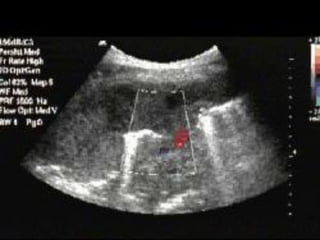

Assessing the IVC

 During inspiration, intrathoracic pressure becomes more

negative, abdominal pressure becomes more positive,

resultant increase in the pressure gradient between the

supra and infra-diaphragmatic vena cava, increases

venous return to the heart.

 Given the extrathoracic IVC is a very compliant vessel

this causes diameter of IVC to decrease with normal

inspiration.

 In patients with low intravascular volume, the inspiration

to expiration diameters change much more than those

who have normal or high intravascular volume.

Estimating theCVP

IVC Diameter (mm) % collapse Estimated CVP (cm

H2O)

<20 >50 5

<20 <50 10

>20 <50 15

>20 0 20

Right atrial pressures, representing central venous pressure, can be estimated

by viewing the respiratory change in the diameter of the IVC.

American society of Echocardiography

2010 guidelines

Assessing the IVC During inspiration, intrathoracic pressure becomes more negative, abdominal pressure becomes more positive, resultant increase in the pressure gradient between the supra and infra-diaphragmatic vena cava, increases venous return to the heart.  Given the extrathoracic IVC is a very compliant vessel this causes diameter of IVC to decrease with normal inspiration.  In patients with low intravascular volume, the inspiration to expiration diameters change much more than those who have normal or high intravascular volume.

Estimating theCVP IVC Diameter(mm) % collapse Estimated CVP (cm H2O) <20 >50 5 <20 <50 10 >20 <50 15 >20 0 20 Right atrial pressures, representing central venous pressure, can be estimated by viewing the respiratory change in the diameter of the IVC.